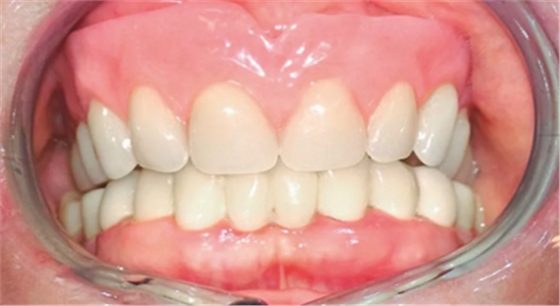

在對義齒的位置進(jìn)行最終調(diào)整后,制作覆蓋義齒(圖11)。試戴覆蓋義齒,達(dá)到咬合平面,臨時決定暫時僅安裝4個Preci附件中的2個,以便于患者更容易適應(yīng)義齒。3周后將所有覆蓋義齒中的配件安裝完畢。

(圖11)